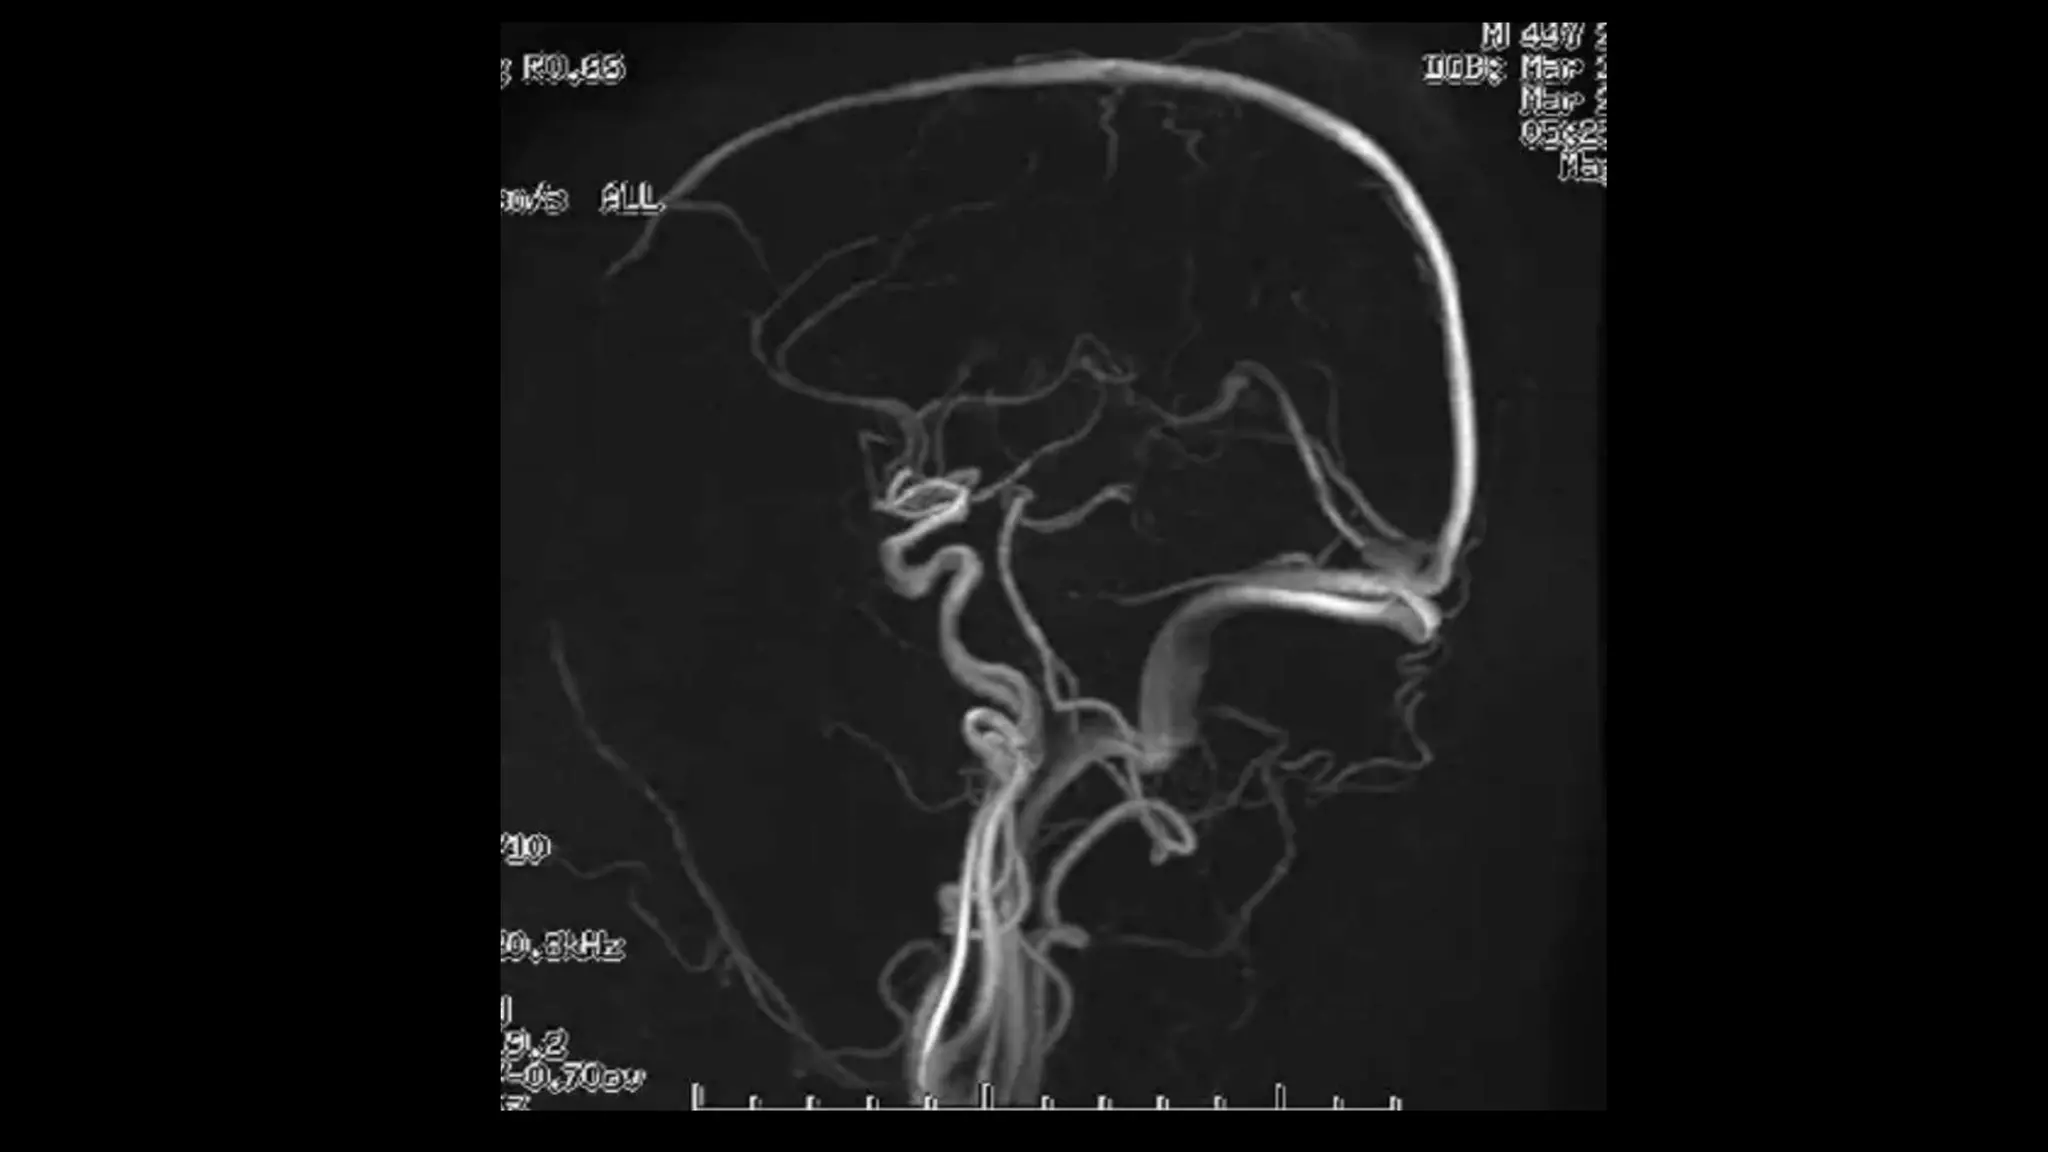

• #63 Here is TOF MIP and VRT MRA showing excellent angiogram due to background suppression and better flow related signal leading to better distal small vessel visibilty

• #64 here is an example of AP VIEW of normal MR angiogram of cervicocranial arterial system